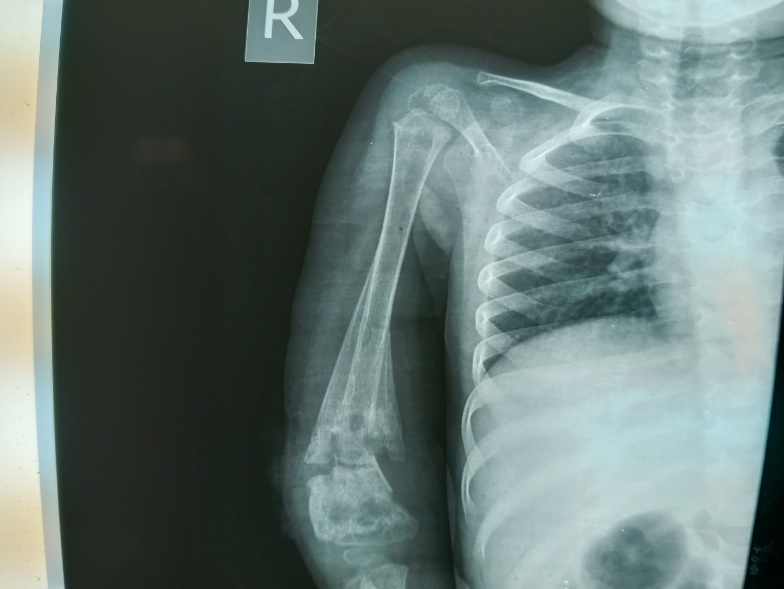

The plain radiograph demonstrated minimally displaced and complete fracture of the distal metadiaphysis of the right humerus with associated mixed sclerotic and lytic foci, areas of medullary sclerosis and lucency, with extensive periosteal reactions having triangular appearance on both cortices; the characteristic Codman’s triangle were noted.

The plain radiograph demonstrated minimally displaced and complete fracture of the distal metadiaphysis of the right humerus with associated mixed sclerotic and lytic foci, areas of medullary sclerosis and lucency more on the fractured segment, with extensive periosteal reactions having triangular appearance on both cortices; the characteristic Codman’s triangle were noted. The presence of the periosteal reactions bilateral also presented the so-called bone-in-bone appearance of chronic osteomyelitis. The lucent foci in the medullary cavity of the humerus are the cloaca. There is associated marked soft tissue swelling more at the affected area with marginal irregularities especially postero-laterally; the discharging sinus. There is a suggestion of dislocation of the elbow joint but with preservation of the shoulder joint (figures 1&2).

Figure 1: Plain radiograph of the right humerus demonstrating complete and displaced fracture of the distal metadiaphysis, cortical thickening, and medullary sclerosis with lucent foci with triangular shaped periosteal reaction (Codman Triangle) attached to both cortices giving the so-called bone-in-bone appearance of chronic osteomyelitis.